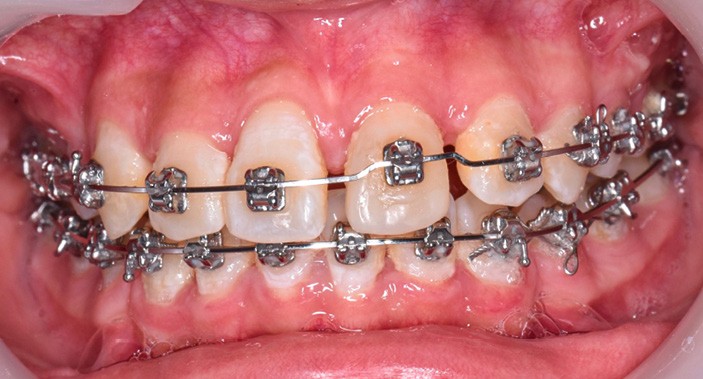

L’objectif du traitement est la correction de la DDA tout en assurant le remplacement de la 21 compromise. Décision a été prise d’extraire 34 et 44, ainsi que 21 et 14. La traction de la 23 a été réalisée à l’aide de forces légères, sur un arc transpalatin (fig. 9). Le nivellement et l’alignement, puis une mécanique par glissement ont permis d’aménager l’espace suffisant à la stratification de la canine. Elle associait un ressort en nickel-titane à des élastiques de Classe II (4 ½ oz, 3/16’’) sur un arc en acier .019×.025. Une phase d’ingression a été réalisée pour ajuster le niveau du bord libre de la canine à celui de l’incisive controlatérale (fig. 10-12).